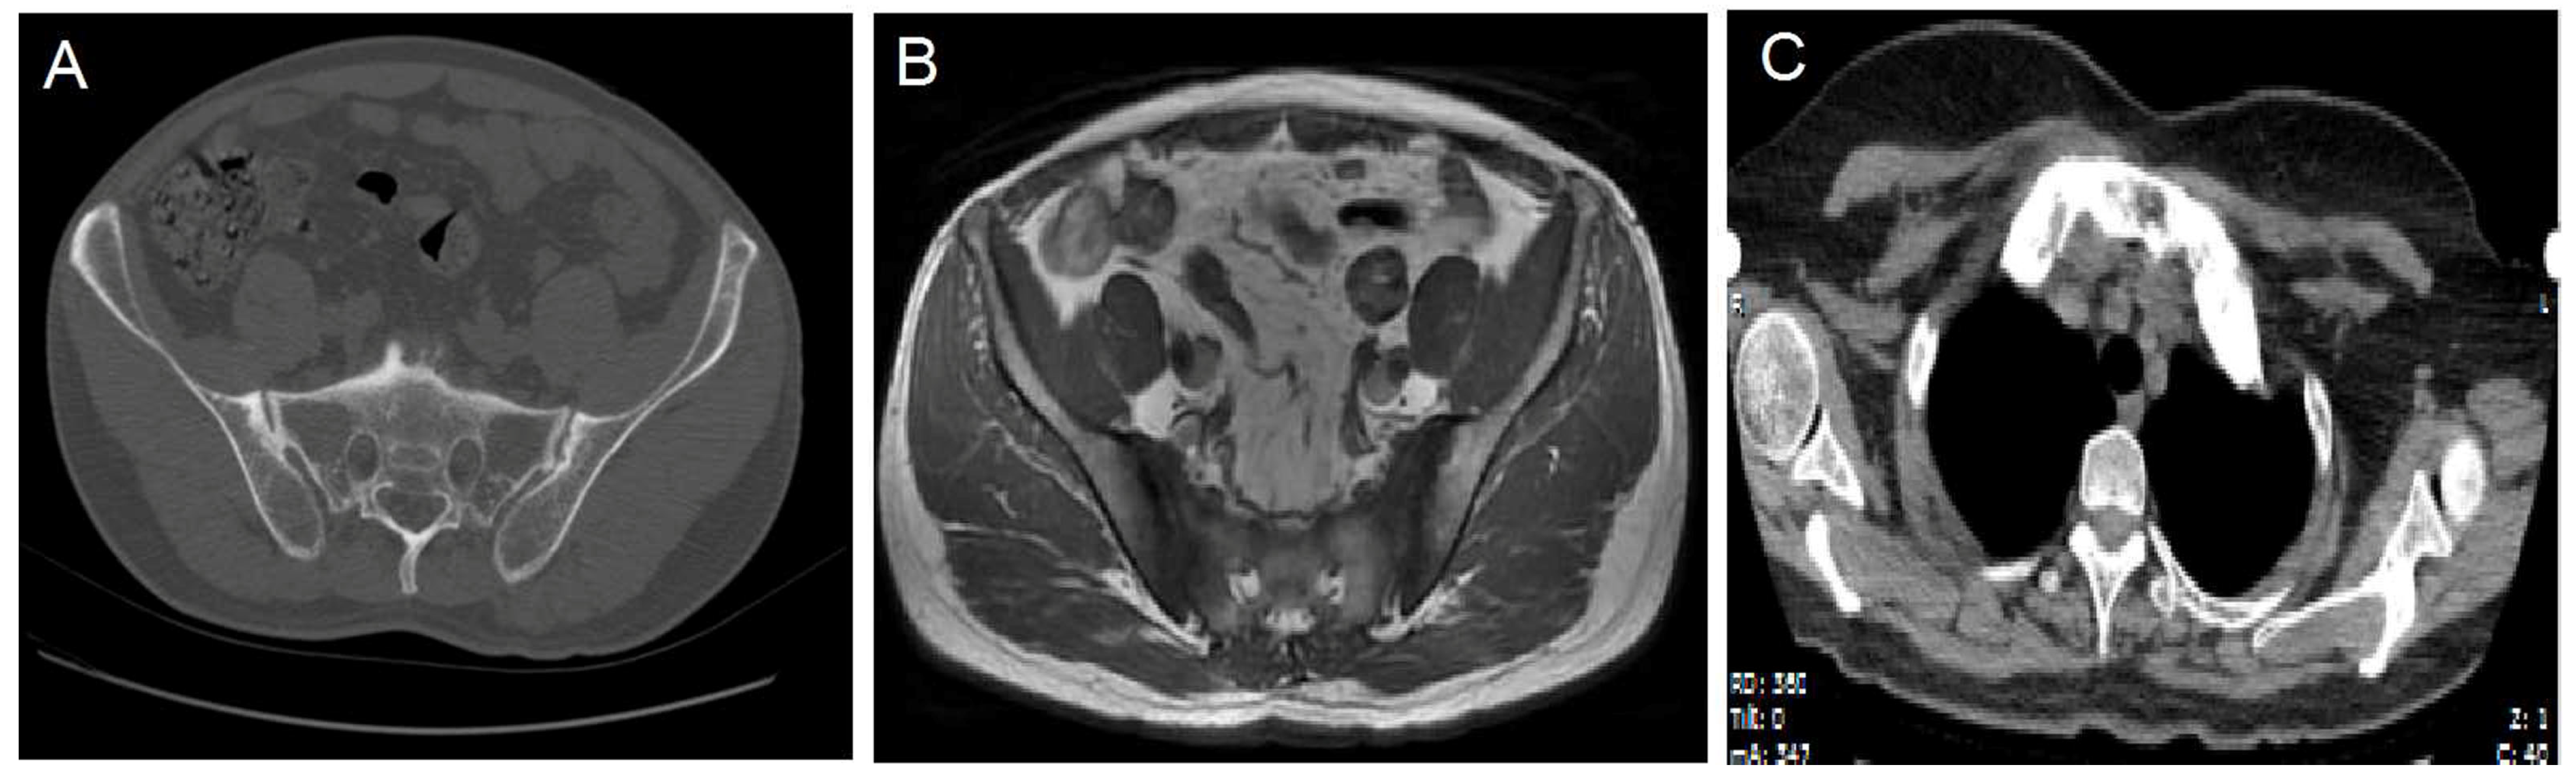

Laboratory tests results showed that human leukocyte antigen B27 (HLA-B27) was positive, hypersensitive C-reactive protein (hs-CRP) was 46.69 mg/L, and erythrocyte sedimentation rate (ESR) was 49 mm/h. A computed tomography (CT) showed multiple sites of wormhole-like bone destruction on the bilateral sacroiliac joint surface, and the right sacroiliac joint was partially fused, in accordance with grade 2 to 3 bilateral sacroiliitis (Figure 2A); a magnetic resonance image (MRI) showed inflammation in the sacroiliac joint (Figure 2B). On the basis of the above results, the diagnosis of AS was determined, and the manifestations met the modified New York criteria in 1984.

Figure 2.

A Computed tomography (CT) image showing multiple sites of wormhole-like bone destruction and partial fusion of right sacroiliac joint (A). A magnetic resonance image (MRI) showing multiple sites of bone marrow oedema on sacroiliac joint surface (B). “Bull’s head sign” on a chest CT (C).

The skin lesions were diagnosed with palmoplantar pustulosis (PPP) after consultation with dermatologists. Notably, a chest CT image showed obviously enlarged sternoclavicular joints with marked hyperostosis and osteosclerosis (Figure 2C), as indicated by the characteristic “bull’s head sign” [8]. A 99Tcm-methylene diphosphonic acid (99Tcm -MDP) single-photon emission computed tomography (SPECT) whole-body bone scan revealed a remarkable radioactive accumulation in the cervical vertebra, sternoclavicular joint, first anterior rib, sternum, and bilateral sacroiliac joints (Figure 3). Thereby, the diagnosis of SAPHO syndrome could be established on the basis of comprehensive clinical assessment.